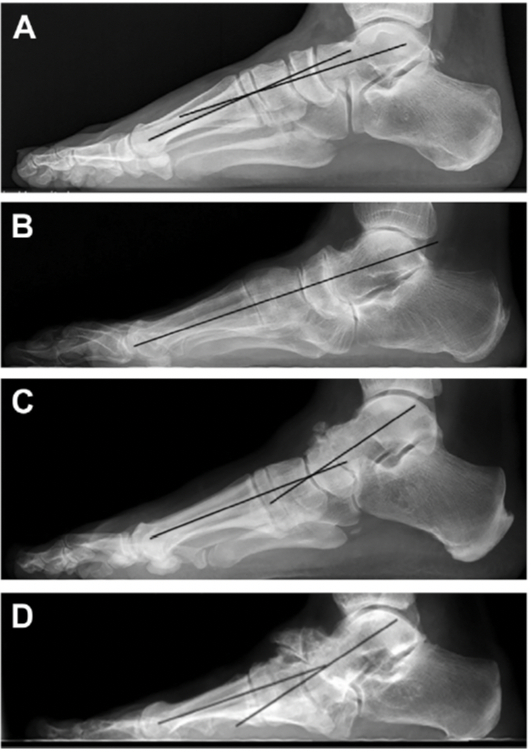

Пример развития деформации стопы на фоне болезни Мюллера—Вейса. На начальных этапах отмечается асимметрия ладьевидной кости, отведение переднего отдела стопы. Далее происходит вывих головки таранной кости и тяжелая многоплоскостная деформация стопы